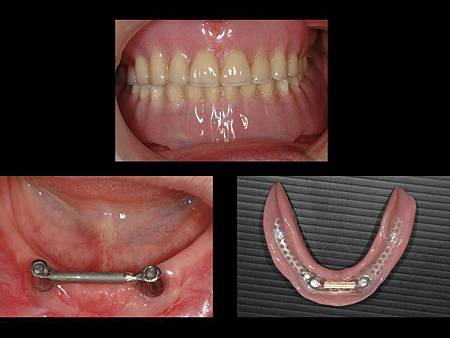

全口無牙的患者, 建議使用人工植牙支撐於假牙下方以增加咬合力

在全口無牙的患者中, 需使用全口活動假牙來恢復咬合功能, 而齒槽脊因時間逐漸萎縮, 活動假牙的固持性會越來越差, 此時可使用人工植牙增加活動假牙下方的支撐, 如此一來假牙較穩固, 患者也才比較可以咬碎食物

患者治療前照相, 隨然佩戴了全口假牙, 但是因為齒槽脊萎縮的關係, 活動假牙不穩定, 患者無法好好的咬碎食物

經評估後植入兩顆xive德國製人工植牙增加下顎支撐

完成圖, 如此一來下顎假牙因下方有植牙支撐, 改善咬合功能 , 以現在的全口假牙標準, 一般建議下顎至少要有植牙2~4顆, 植牙越多的話患者咬合功能可以恢復得更多